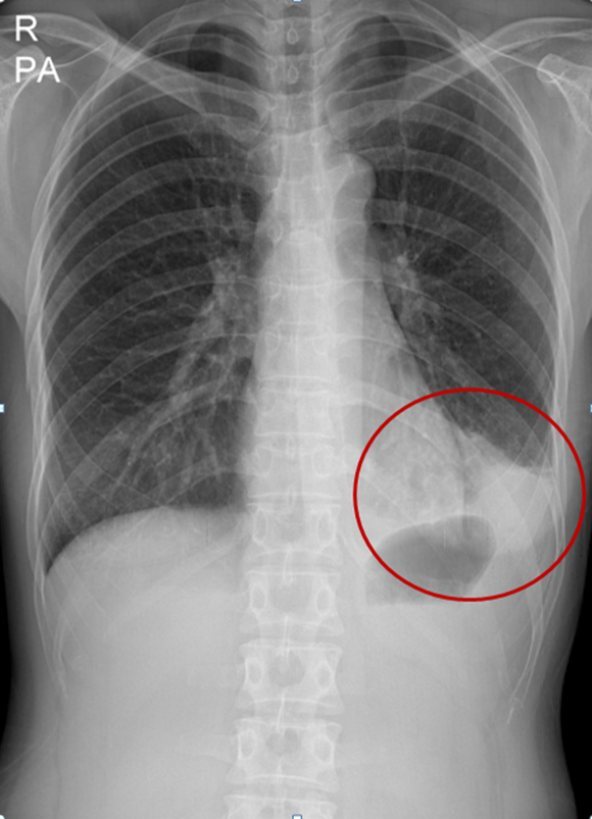

폐렴은 임상적인 증상과 X-선 검사를 통하여 진단하게 된다. 폐렴으로 진단된 후의 진료에서 가장 중요한 결정 중의 하나는 입원 여부의 결정이다. 환자의 중증도나 사망 위험도에 따라 적절하게 외래 치료 혹은 입원 치료를 결정하여야 하는데 노년층에서는 여러 동반 질환이 있는 경우가 많아 임상적인 안정상태에 도달하는 기간이 길어지므로 젊은 사람에 비해서 긴 회복기간이 필요하게 된다. 따라서 여러 동반 질환이 있는 노년층에서 입원치료 후 퇴원 시점을 결정할 때에는 조기 재활 치료를 포함한 추가적인 조치가 필요한지를 평가해야 한다.